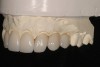

Fig 7. Preoperative occlusal view; note the left

second premolar is rotated 90°, and the lateral incisors had a significant size disparity.

Figure 7

The patient was congenitally missing her maxillary left lateral incisor and mandibular left central incisor, and was unhappy with the lack of symmetry in her dentition, broken edges on her front teeth, and unappealing teeth coloring. The maxillary left canine was positioned in the left lateral incisor space and had been restored with unsightly bonding to close the gap. Her maxillary left second premolar was rotated 90 degrees, and her maxillary and mandibular incisal edges were broken and worn (Figure 7).